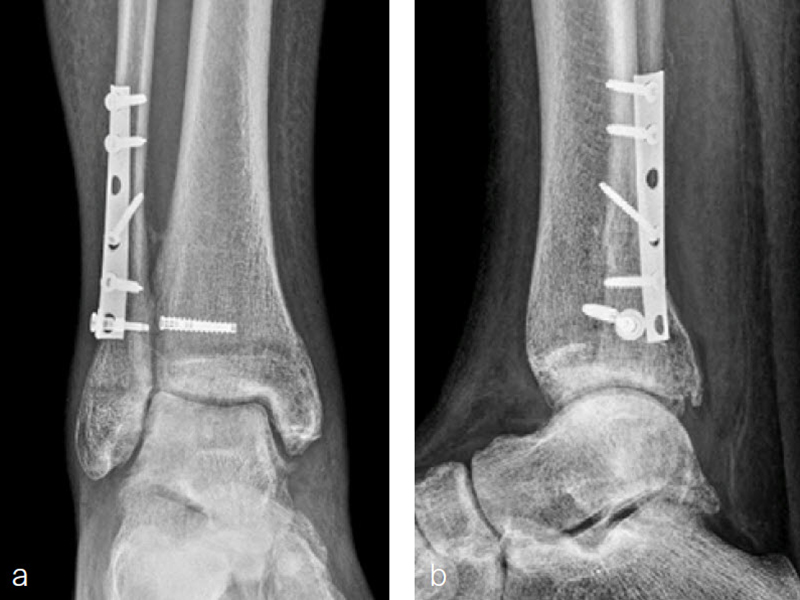

A 34-year-old woman was injured while riding a motor scooter sustaining an ankle fracture with associated syndesmotic injury (Fig 6a). The fibula was reduced anatomically and stabilized with a 1/3 tubular plate (Fig 6b). The unstable syndesmosis was reduced and provisionally stabilized with a K-wire and clamp (Fig 7) before FIBULINK Implant System implantation (Fig 8). The patient had an uneventful recovery (Fig 9).